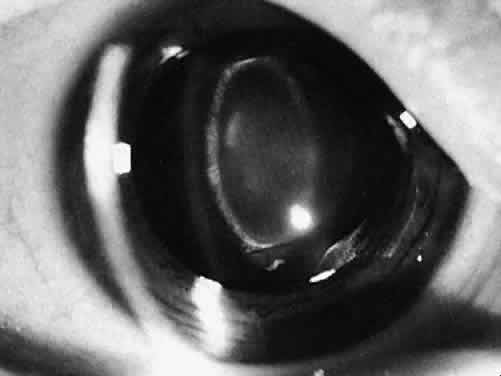

Visual Acuity and Signs of Visual Function

Ultimately, it is the measured or estimated level of visual acuity or acuity potential that determines the need for cataract surgery. If either the measured or the estimated decrease in visual acuity produced by the cataract is sufficient to prevent adequate visual development or if signs of significantly decreased visual acuity, such as strabismus or poor central fixation, are present, cataract surgery is indicated. Use of the Teller visual acuity cards at periodic intervals can help to measure visual acuity.10 In some children, visual acuity that is below normal or decreasing can be documented accurately to support the decision to perform cataract surgery (Figs. 4 and 5). Care must be taken in interpreting Teller visual acuity data because the normal levels in young infants and children are low and span a wide range. The Teller acuity card measurement of grating visual acuity may severely underestimate the level of visual loss in patients with cataracts and amblyopia.11

Fig. 4. Posterior lenticonus type of cataract. When the child was 1 year old, the cataract increased in size, and the posterior portion of the lens became increasingly opaque. Surgery was recommended.